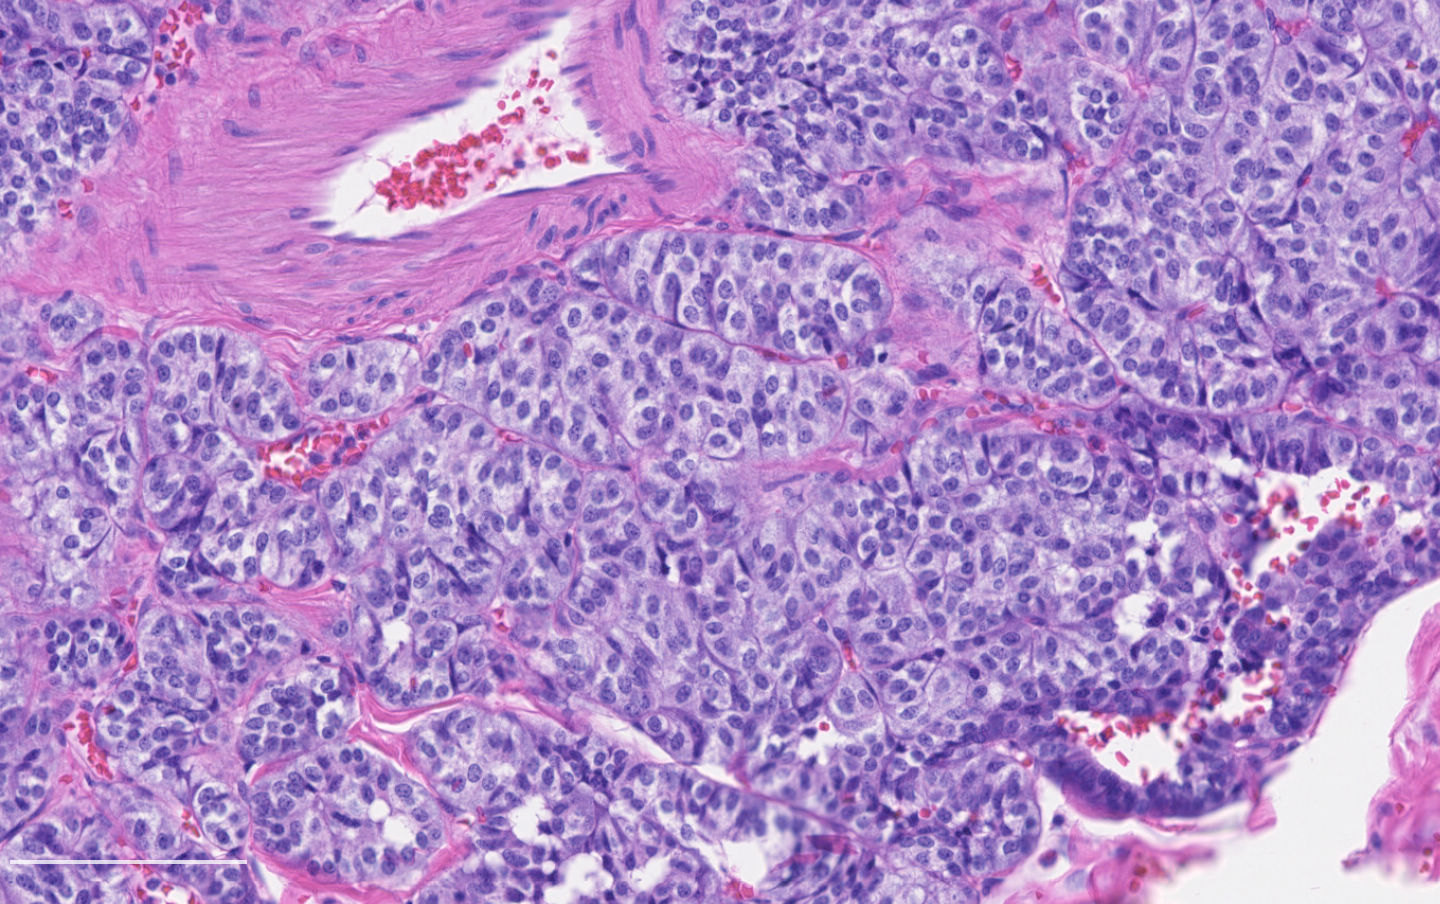

- Neuroendocrine histologic patterns similar to typical carcinoids: organoid, trabecular, rosette formation, papillary, pseudoglandular, follicular

- Tumor cells are as typical carcinoid: uniform with a polygonal shape, round to oval nuclei with salt and pepper chromatin and inconspicuous nucleoli, along with moderate to abundant eosinophilic cytoplasm

- Greater pleomorphism than for typical carcinoid is common (Arch Pathol Lab Med 2010;134:1628)

- Spindle cells and clear cell features can be seen

- Stroma is fine and highly vascularized; hyalinization, cartilage or bone formation are possible

Contributed by Philippe Joubert, M.D., Ph.D.

- A patient undergoes a lobectomy for a well circumscribed nodule. On H&E slide, the tumor exhibits a well differentiated neuroendocrine morphology and you observe the histologic features presented in the image. Which of the following statements is true?

B. It is defined as a well differentiated neuroendocrine tumor with 2 - 10 mitoses per 2 mm² or foci of necrosis. The picture shows a carcinoid lung tumor with a classical neuroendocrine morphology and 2 mitoses in 1 high power field. Even though the whole tumor is not presented here, the presence of 2 mitoses is sufficient for an atypical carcinoid diagnosis.